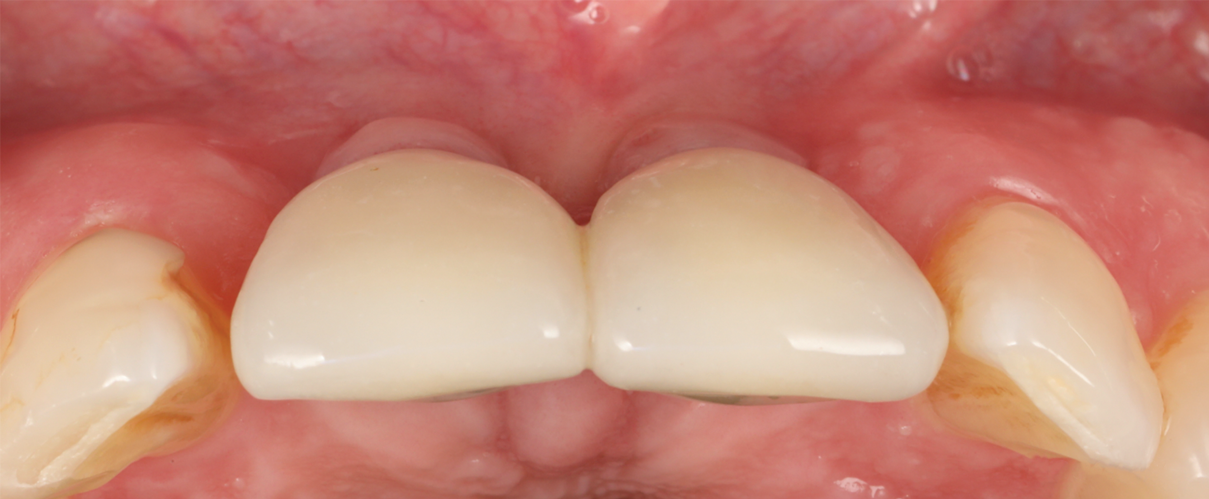

Figure 14 depicts the final outcome at 1 year (which can be compared to the pretreatment photograph in Figure 1). Figure 15 through Figure 18 show clinical comparisons of the outcome at baseline and 1 year, while Figure 19 and Figure 20 provide an ultrasonographic characterization of the soft tissue at baseline and 1 year. The facial probing depths at 1 year were 3-3-3 mm for implant No. 8 and 3-2-3 mm for implant No. 9. The patient was highly satisfied with the esthetic outcomes and overall treatment.

Fig 14. Final outcome at 1 year.

Figure 14

Fig 16. Clinical comparison of the volumetric gain obtained with the intervention, frontal views. Fig 15: Frontal view at baseline. Fig 16: Frontal view at 1-year post-treatment.

Figure 16